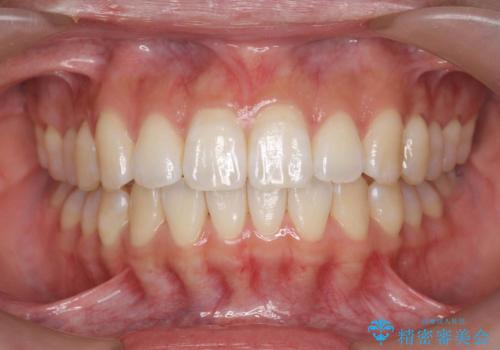

インビザラインライトは全14枚のマウスピースで行う軽度なガタつきなどの改善を目的とする矯正治療です。(約3.5ヶ月)

今回の治療では追加でマウスピース治療を行なったため、半年弱の治療期間となりました。